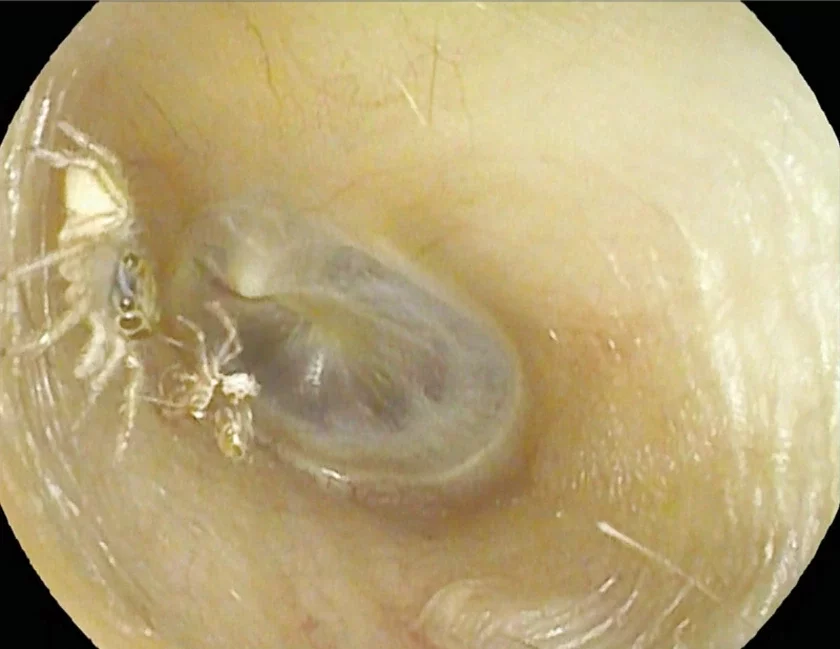

И действительно, когда врачи осмотрели пациентку, они быстро заметили маленького паука, который просто занимался своими делами в ушном канале.

Этот же конкретный случай на Тайване был действительно интересным также не только тем, что паук оставил после себя. Один из врачей признался, что до этого не видел ни паука, ни его оставленный в ухе экзоскелет.

Думать о таком бывает страшно, но ушные насекомые обычно не вызывают серьезных врачебных проблем (хотя их нужно удалять как можно быстрее, чтобы избежать риска повреждения уха или инфекции). В последнем случае врачи использовали аспирационную канюлю (специальную всасывающую трубку) через отоскоп, чтобы высосать паука и его «сброшенную одежду». В результате женщина «счастливая пошла домой». О дальнейшей судьбе паука, к сожалению, ничего неизвестно.